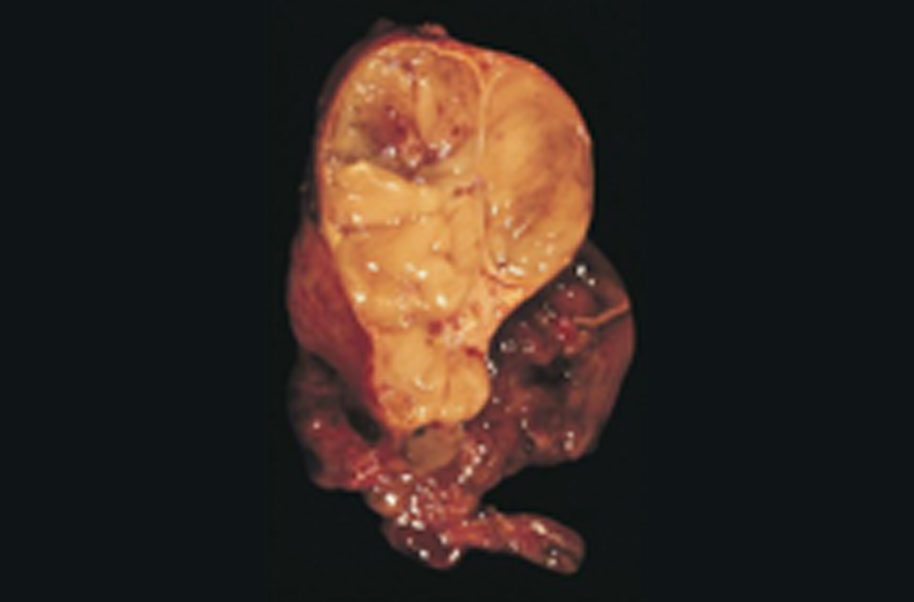

Thymoma and thymic carcinoma are diseases in whichmalignant (cancer) cells form on the outside surface of the thymus. Thymoma is linked with myasthenia gravisand other autoimmune diseases. Signs And symptoms of thymoma and thymic carcinoma include a cough and chest pain